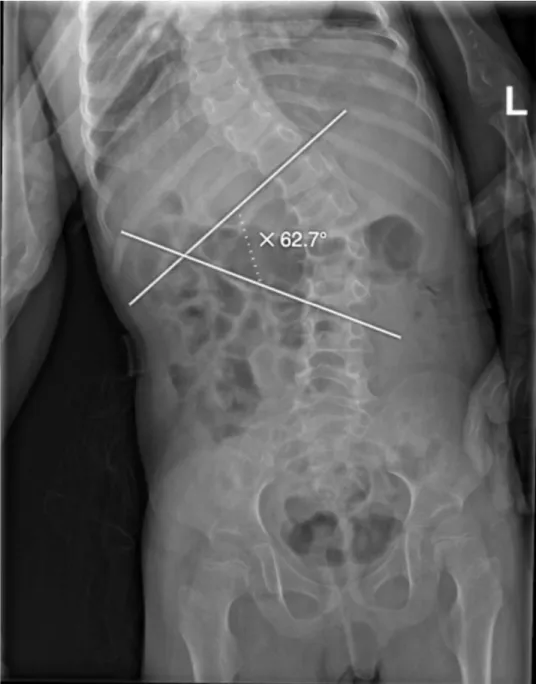

At the time of her most recent hospitalization, she presented with an episode of epistaxis, multiple episodes of hematemesis, and a purpuric rash. Physical examination revealed several dysmorphic features, including micrognathia, broad nasal tip, hypertelorism, thick eyebrows, large, low-set ears, and a short neck. Musculoskeletal examination revealed marked hypotonia in both upper and lower extremities, cavovarus feet, scoliosis with a Cobb angle of 62.7°, and hypoplastic nails, particularly in the fifth fingers (Figures 2,3). Her skin was dry with absent body hair and a purpuric rash (Figure 4).

Figure 2: Spine X-ray showing scoliosis with a Cobb angle of 62.7°, indicating a severe spinal curvature.